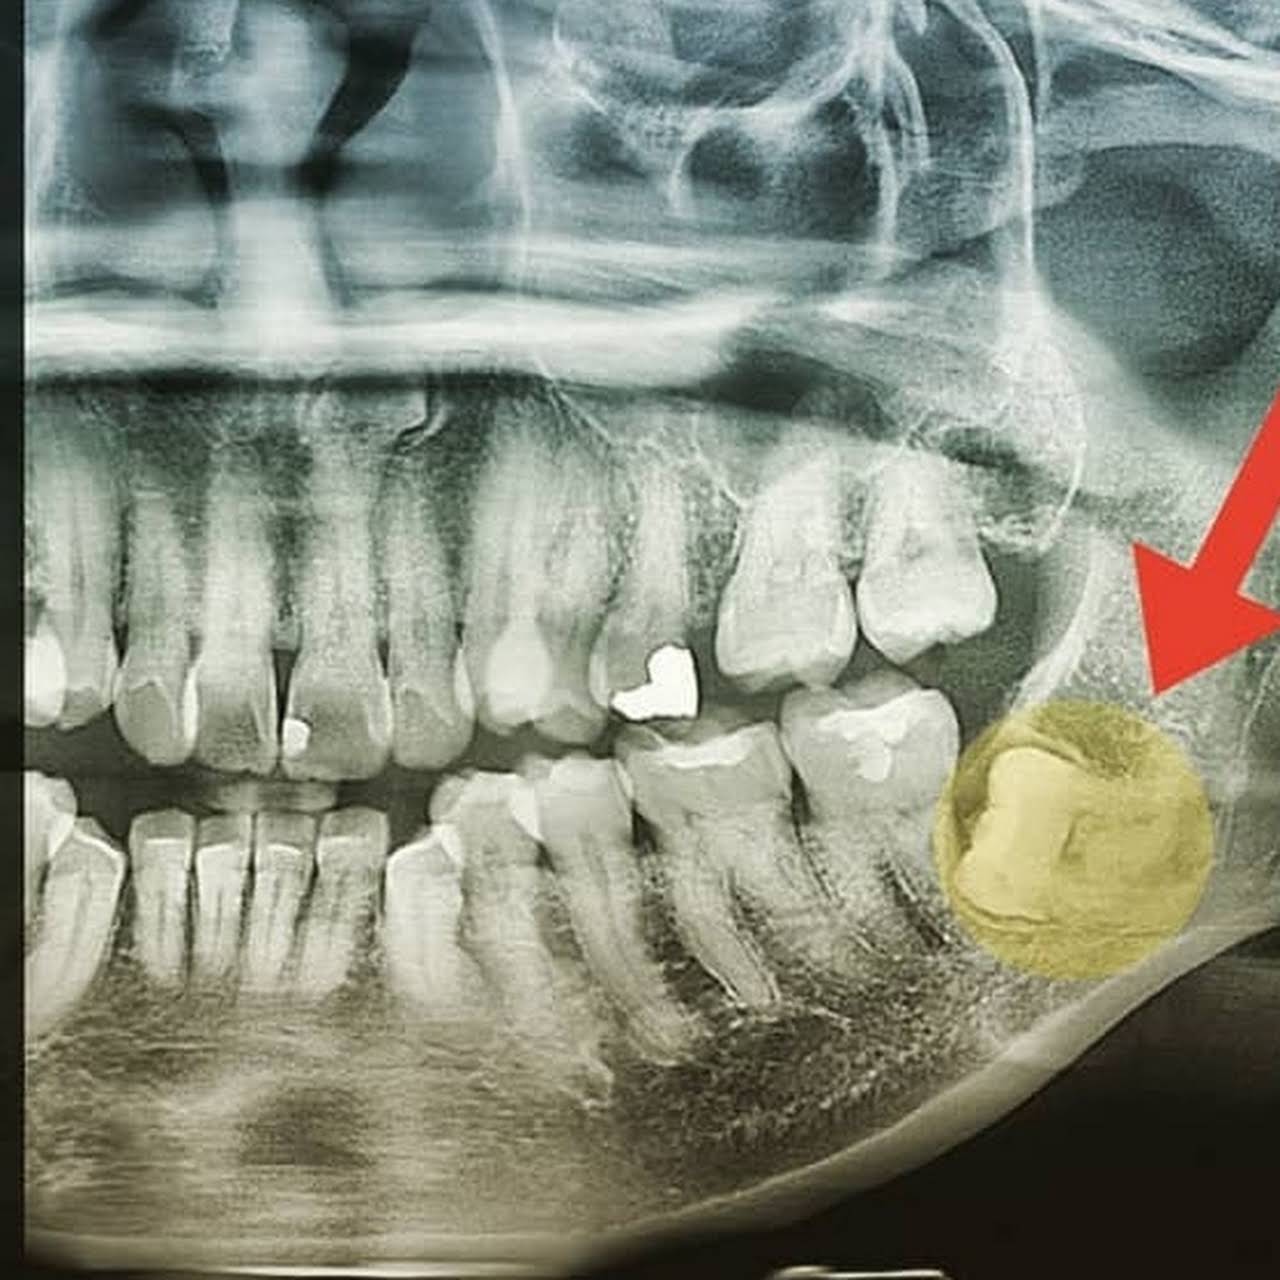

Foto rontgen periapikal 1x di pondok gigi harga terbaru 2021 hdmall. Biasanya harga rontgen gigi lebih besar di rumah sakit swasta dibandingkan di rumah sakit umum. X-ray jenis ini digunakan untuk mencari masalah gigi di bawah permukaan gusi atau di dalam rahang seperti gigi bertabrakan abses kista tumor dan perubahan tulang yang diakibatkan penyakit.

Radiografi gigi tipe occlusal juga dapat mendeteksi kelainan anatomi pada dasar mulut atau langit-langit impaksi gigi hingga tumor. Alasan dokter gigi minta anda foto panoramik dulu sebelum tindakan. Juga dari 1 tahun 3 tahun panorama gigi x ray harga mesinDan apakah panorama gigi x ray harga mesin tersebut 1 tahun 2 tahun atau 5 tahun.

Periapical X-ray akan menunjukkan keseluruhan gigi mulai dari mahkota gigi yang terlihat sampai pada akar dan tulang yang menyokong gigi tersebut. Kemaskini terbaru Dec 2021. Single-contrast studies fill the lumen with radiopaque material outlining the structure.